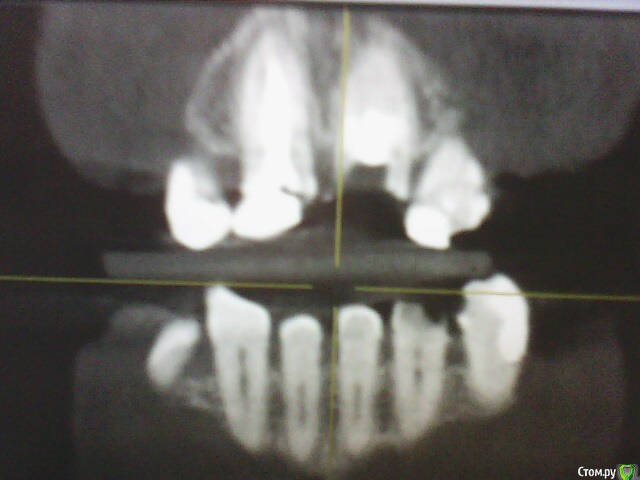

ОльгаS Опубликовано 16 декабря, 2014 Автор Поделиться Опубликовано 16 декабря, 2014 Оба раза на консультации присутствовали и имплантолог и ортопед, добавлю еще снимки: Ссылка на комментарий